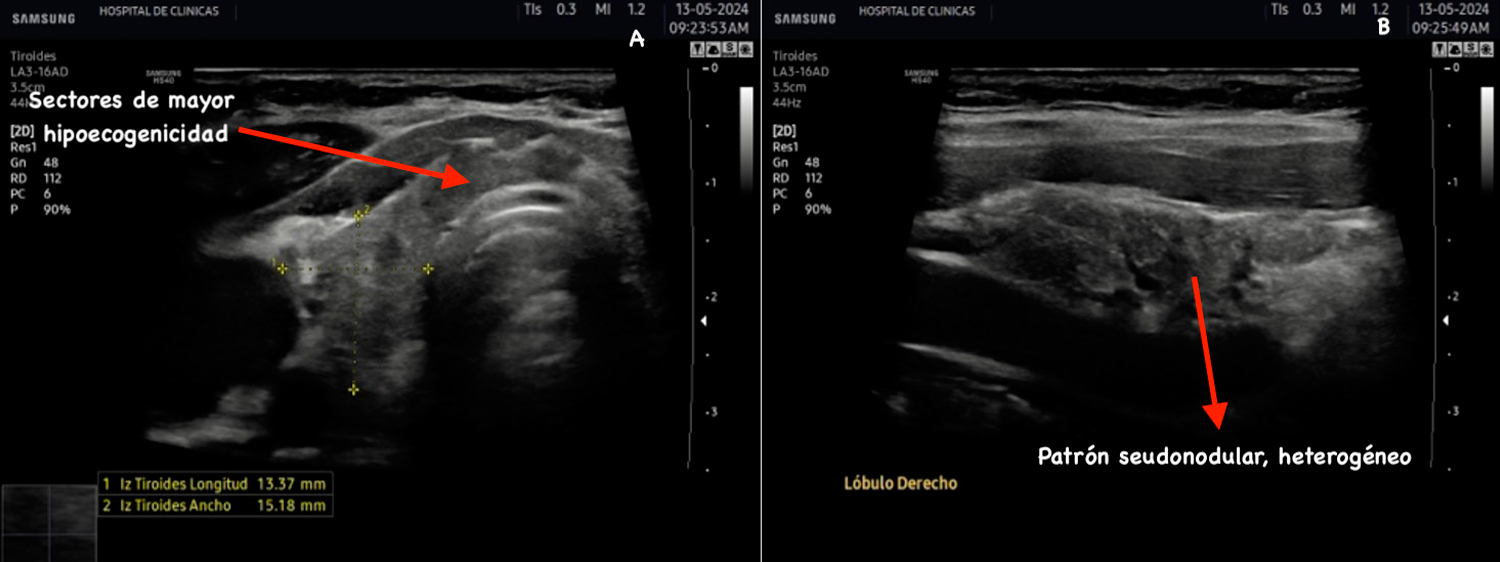

La fase aguda es transitoria, generalmente comienza con infiltración linfocítica en el istmo y en los sectores anteriores de los lóbulos tiroideos representados con manchas hipoecoicas homogéneas y uniformes, además de áreas con márgenes mal definidos. La propagación de la infiltración confiere este aspecto en ambos lóbulos. En la fase subaguda se propaga esta infiltración al resto de la glándula acompañada de hipervascularización irregular7.

La hipoecogenicidad del parénquima glandular se correlaciona con el grado de infiltración linfocitaria, atrofia de los folículos y disminución del contenido coloide. Esto genera menos reflexión de las ondas sonoras y, por lo tanto, menor ecogenicidad6. Se puede encontrar además aspecto micro o macronodular. Se denominan seudonódulos a las áreas de intensa infiltración linfocitaria local, las cuales deben ser diferenciadas de los nódulos verdaderos que requieren otro seguimiento6. En la figura 6 se aprecian estas características comentadas.

Figura 6: Corte transversal y longitudinal de tiroides de paciente con tiroiditis de Hashimoto. Se señala la disminución de la ecogenicidad, estructura

heterogénea, seudonodular.